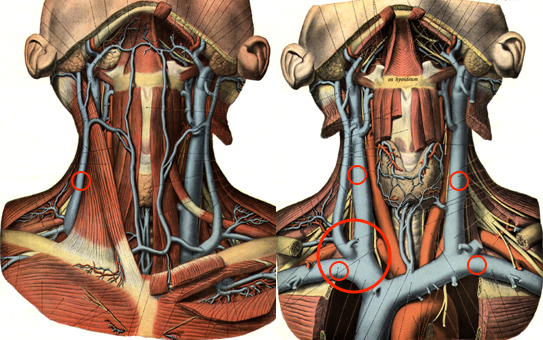

Diese Anforderungen treffen ausschließlich auf die proximale rechte Vena jugularis / Vena anonyma zu, die deshalb als Standardzugang verwendet werden sollte, zumal diese Punktion auch besonders einfach unter sonographischer Kontrolle erfolgen kann.

Goldstandard ist die Punktion der rechten Vena jugularis/anonyma supraklavikulär nach oder unter sonographischer Kontrolle. Die Sonographie muß Lagevarietäten klären und Thrombosen nach früherer Katheterisierung ausschließen.

Die Vena jugularis/ Vena anonyma kann nach Yoffa zwischen medialem und lateralem Kopf des Musculus sternocleidomastoideus von ventral punktiert werden oder horizontal von lateral. Diese Methode wurde 1972 von den amerikanischen Herzchirurgen Garcia, Mispireta und Pinho nach ausführlichen anatomischen Präparationen als einfachster und ungefährlichster Zugang beschrieben. Das Zielgebiet, der Zusammenfluß von Vena jugularis und Vena subclavia zur Vena anonyma ist so groß, dass die Punktion auch ohne Sonographie immer beim ersten Stich gelingt.

Die in der Anästhesie verbreitete Punktion der distalen Vena jugularis ist komplikationsträchtig und sollte vermieden werden. Normalerweise liegt die Vena jugularis lateral der A. carotis.

Bei der schädelnahen Punktion muß der Kopf nach links gedreht werden, weil sonst das Kinn im Weg ist. Dadurch rotiert die Vene vor die Arterie und das Lumen wird schlitzförmig.

Vor der Einmündung in die Vena anonyma macht die Jugularvene einen Knick von 45 Grad nach dorsal. Diatator, Einführschleuse und Katheter stoßen dort an der Venenvorderwand an und erzeugen Intimaläsionen, die bei 30% der Patienten später zur Thrombose führen.

Darüberhinaus geht der Katheter durch die ganze Breite des Musculus sternocleidomastoideus. Dies führt zu einer rein/raus-Bewegung des Katheters bei jedem Schlucken und jeder Kopfbewegung. Das begünstigt einerseits das Einwandern von Hautkeimen in den Punktionskanal, andererseits werden Fibrinablagerungen auf der Katheteroberfläche an der Punktionsstelle abgestreift. Dadurch kommt es zu einer Akkumulation von Fibrin und thrombotischem Material an der Venenwand und um den Katheter.

Argumente gegen Punktion von links

Von links eingeführte Katheter stoßen in der in mehreren Ebenen gewundenen Vena brachiocephalica an die Venenwand an und verursachen Intimaläsionen und Thrombosen. Die Wandschäden sind umso schlimmer, je steifer der Katheter ist. Die schlimmsten Schäden rufen die in der Intensivmedizin üblichen lage bore Katheter hervor.